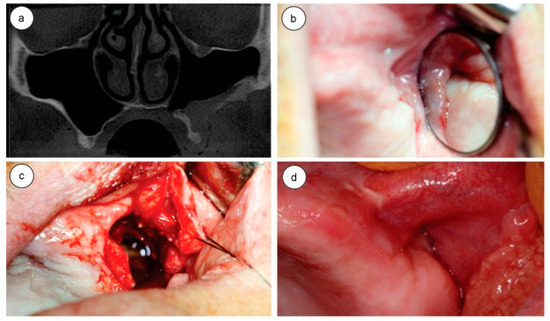

The patient was treated with 875 mg amoxicillin + 125 mg Clavulanate Potassium 1 capsule every 12 hours for 14 days, 1 tablet 100 mg Nimesulide every 12 hours for 4 days, and 1 tablet 750 mg paracetamol every 6 hours in case of pain or fever. After 10 days, the suture was removed, upon which a tiny buccosinusal communication was noted. We opted to wait for a better cicatrization of the area to confirm the clinical picture and eventually perform reconstructive surgery. A CT scan was performed in the immediate postoperative period, in which the complete removal of ectopic structures and the preservation of the maxillary roof sinus and orbital floor could be observed (Figure 2a).

Within 2 weeks after surgery, the patient showed an improvement with respect to respiration and phonation. Clinical examination showed a buccosinusal communication, and after certifying that the maxillary sinus was healthy through its irrigation with 0.9% saline, the communication was closed with the combination of a marginal flap with a vestibular flap performed under local anesthesia (Figure 2b,c).

After a 3-year postoperative follow-up period, the patient has not shown any sinusitis, buccosinusal communication, diplopia, limitation of ocular movements, or any other complaints. The patient is still being followed up (Figure 2d).

Figure 2. (a) Postoperative computed tomography coronal slice showing the healing sinus; (b) postoperative oroantral communication; (c) oroantral communication closure surgery; (d) postoperative 3 years follow-up.